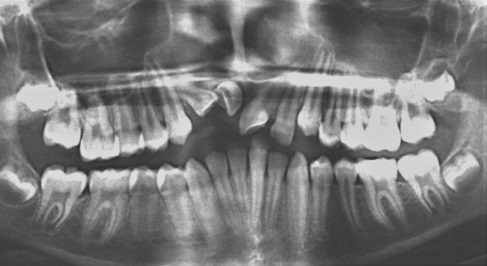

The American Association of Orthodontists recommends giving kids their first orthodontic exam and screening at age 7, which is usually the age when first molars and incisors grow. We screen our younger patients in our dentist office, making it easier for them to get the beautiful smile they deserve.

Certain orthodontic problems should be addressed at an early stage to avoid alignment issues later in life and to facilitate orthodontic treatment in the future — and our board-certified orthodontists are here to help. After examining your child’s mouth, we’ll make a recommendation on whether to monitor their growth and do a follow-up after a certain number of months or to make a recommendation for early orthodontic treatment.

Orthodontic screening at age 7 is simple, safe, and highly recommended.

Our knowledgeable team will formulate a tailored strategy to address any possible orthodontic concerns and determine at what age your child might benefit from braces. And, we’ll discuss what type of braces might be a good fit for your child’s mouth.